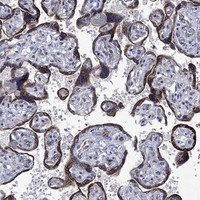

Cytoplasmic expression in several tissues, mainly in placenta.

The IHC image panel to the right display selected tissues that give a visual summary of the protein expression profile.

Placenta

Multiplex immunofluorescence staining of kidney shows cytoplasmic localization in endothelia and podocytes.